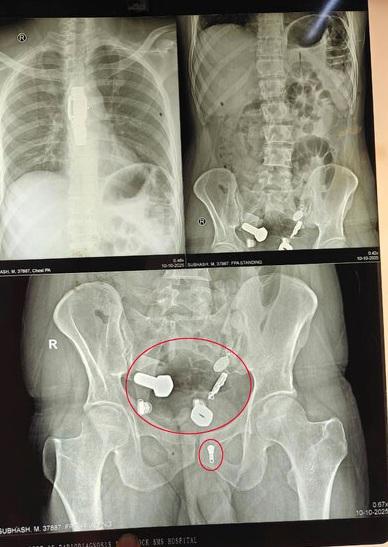

又一異食癖的誇張案例……英國《鏡報》等媒體報道,印度齋浦爾(Jaipur)一名34歲男子因劇烈腹痛、無法飲水進食,本月9日被家人送往醫院急症室就診。醫生替他做X光等檢查,驚見他食道裡竟卡著一隻手錶,大腸裡還有多塊鐵片、螺絲帽、螺絲、繩子、吊墜等物品,讓醫療團隊十分驚訝。

手術過程被拍下,醫生從男子腹部的小切口拉出手錶。(互聯網) X光檢查發現,男子腸道裡有鐵片、螺絲帽、螺絲等異物。(互聯網) 醫生從男子的食道和腸道取出手錶、鐵片、螺絲帽、螺絲和繩子等異物。(互聯網) X光檢查發現,男子有手錶卡著食道,腸道裡有鐵片、螺絲帽、螺絲等異物。(互聯網)